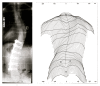

Background: Spinal fusion surgery is currently recommended when curve magnitude exceeds 40-45 degrees. Early attempts at spinal fusion surgery which were aimed to leave the patients with a mild residual deformity, failed to meet such expectations. These aims have since been revised to the more modest goals of preventing progression, restoring 'acceptability' of the clinical deformity and reducing curvature.In view of the fact that there is no evidence that health related signs and symptoms of scoliosis can be altered by spinal fusion in the long-term, a clear medical indication for this treatment cannot be derived. Knowledge concerning the rate of complications of scoliosis surgery may enable us to establish a cost/benefit relation of this intervention and to improve the standard of the information and advice given to patients. It is also hoped that this study will help to answer questions in relation to the limiting choice between the risks of surgery and the "wait and see - observation only until surgery might be recommended", strategy widely used. The purpose of this review is to present the actual data available on the rate of complications in scoliosis surgery.

Conclusion: Scoliosis surgery has a varying but high rate of complications. A medical indication for this treatment cannot be established in view of the lack of evidence. The rate of complications may even be higher than reported. Long-term risks of scoliosis surgery have not yet been reported upon in research. Mandatory reporting for all spinal implants in a standardized way using a spreadsheet list of all recognised complications to reveal a 2-year, 5-year, 10-year and 20-year rate of complications should be established. Trials with untreated control groups in the field of scoliosis raise ethical issues, as the control group could be exposed to the risks of undergoing such surgery.